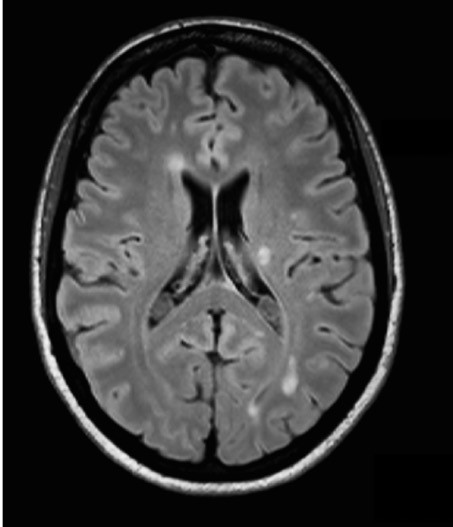

Afin de compléter votre bilan étiologique vous réalisez l’IRM cérébrale suivante :

Question 10 : Indiquez les items vrais

Le cliché correspond à une IRM cérébrale en séquence FLAIR. La séquence FLAIR correspond à une séquence T2 (la substance blanche est grise et la substance grise est blanche [par opposé au T1 qui est une séquence plus anatomique avec la substance blanche qui est blanche et la substance grise qui est grise]) avec annulation du signal des molécules d’eau (donc du LCR). Les liquides (et donc le LCR) apparaissent donc noirs sur le FLAIR et non pas blancs à la différence du T2. Cette séquence est très utile pour identifier les lésions périventriculaires de la sclérose en plaques. Elle permet ici d’identifier plusieurs lésions périventriculaires et juxta-corticales, donc dans 2 territoires différents. Seule l’IRM cérébrale en séquence T1 avec injection de gadolinium peut dire si les lésions sont d’âges différents (les lésions récentes se rehaussent après injection de gadolinium).